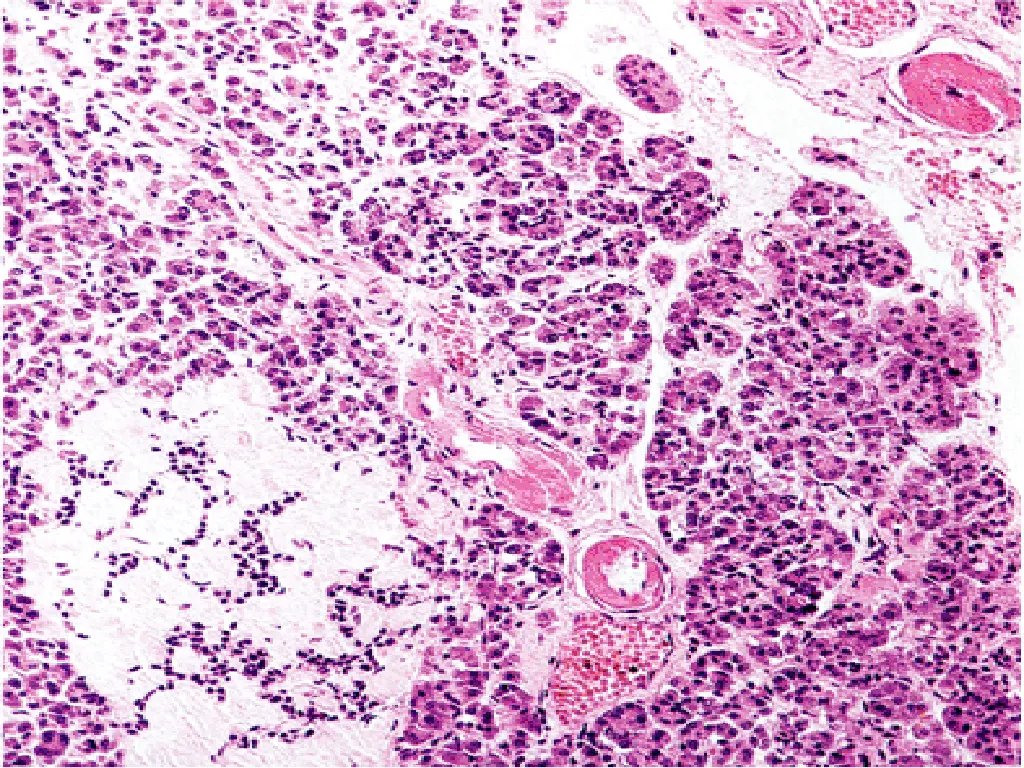

T1DM, PATHOGENESIS 2- AUTOIMMUNITY: Patients who die shortly after the onset of the disease often exhibit an infiltrate of mononuclear cells in and around the islets of Langerhans, termed insulitis 22

Insulitis 23

T1DM, Autoimmunity - Cell-mediated immune mechanisms are fundamental to the pathogenesis of T1DM ,CD8+T lymphocytes pre-dominate, although some CD4+cells are also present. - The infiltrating inflammatory cells also elaborate cytokines, for example, IL-1, IL-6, interferon-alpha, and nitric oxide, which may further contribute to B cell injury. - An autoimmune origin for T1DM was initially suggested by the demonstration of circulating antibodies against components of the B cells (including insulin itself) in most newly diagnosed children with diabetes. 24

PATHOLOGY - Lymphocytic infiltrate in the islets (insulitis), sometimes accompanied by a few macrophages and neutrophils - As the disease becomes chronic, the B cells of the islets are progressively depleted of Beta cells - Fibrosis of the islets is uncommon. - In contrast to T2DM, deposition of amyloid in the islets of Langerhans is absent in T1DM. - The exocrine pancreas in chronic T1DM often exhibits diffuse interlobular and interacinar fibrosis, accompanied by atrophy of the acinar cells. 27